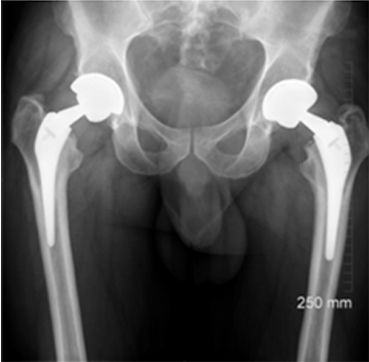

This case involves a 67-year-old gentleman who faced a series of complications due to hip trauma he had experienced over 50 years ago. After his primary and revision surgeries, and subsequent three hip replacements, he was left with a failing hip implant. His most recent hip replacement lasted 13 years before massive circumferential acetabular osteolysis caused the cup to loosen. Imaging revealed anterior and medial wall deficiencies, while the posterior column remained intact. The patient had a metal-on-polyethylene (MoP) bearing, which over time led to the wear of the polyethylene liner, triggering an inflammatory reaction and bone loss due to polyethylene debris.

The surgical plan required a custom 3D-printed acetabular cup, designed specifically for the patient's anatomy. The implant was designed with three flanges for optimal fixation. The surgery involved a posterior approach, with meticulous bone preparation to minimize further bone loss and ensure the custom implant fit securely.

This case represents ALTR with MoP. ALTR was characterized by massive osteolysis of the pelvic bone, which was most likely caused by polyethylene wear debris. This case underscores the complexity of revision hip surgeries and highlights the value of custom 3D-printed implants for achieving secure fixation and improving patient outcomes despite significant bone loss. Update at 7 years post operative is that the patient has excellent hip function and more can be seen in this paper:

Durand‐Hill, M., Henckel, J., Di Laura, A., & Hart, A. J. (2020). Can custom 3D printed implants successfully reconstruct massive acetabular defects? A 3D‐CT assessment. Journal of Orthopaedic Research®, 38(12), 2640-2648.5.https://doi.org/10.1002/jor.24752